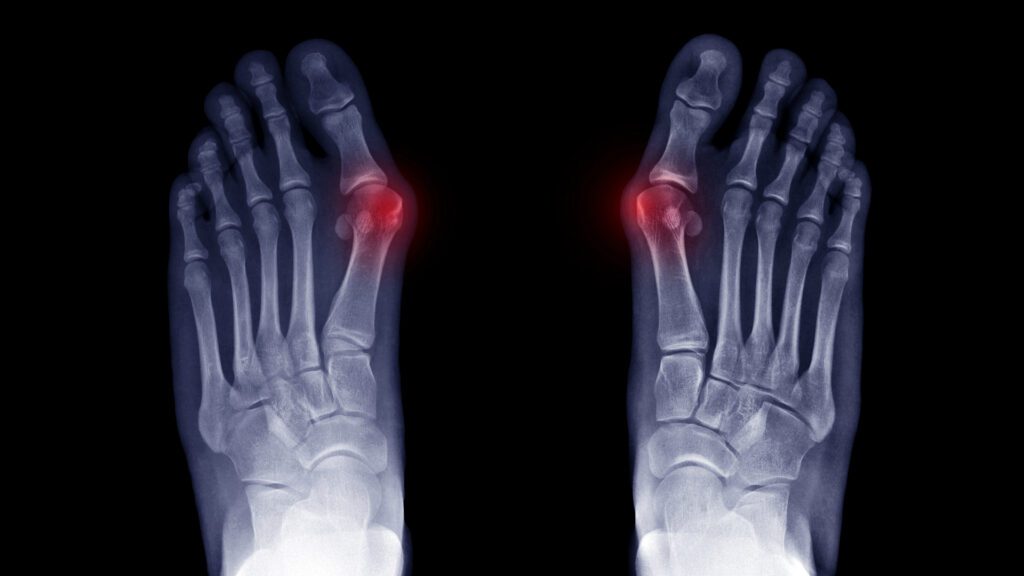

Forward Foot & Ankle Center